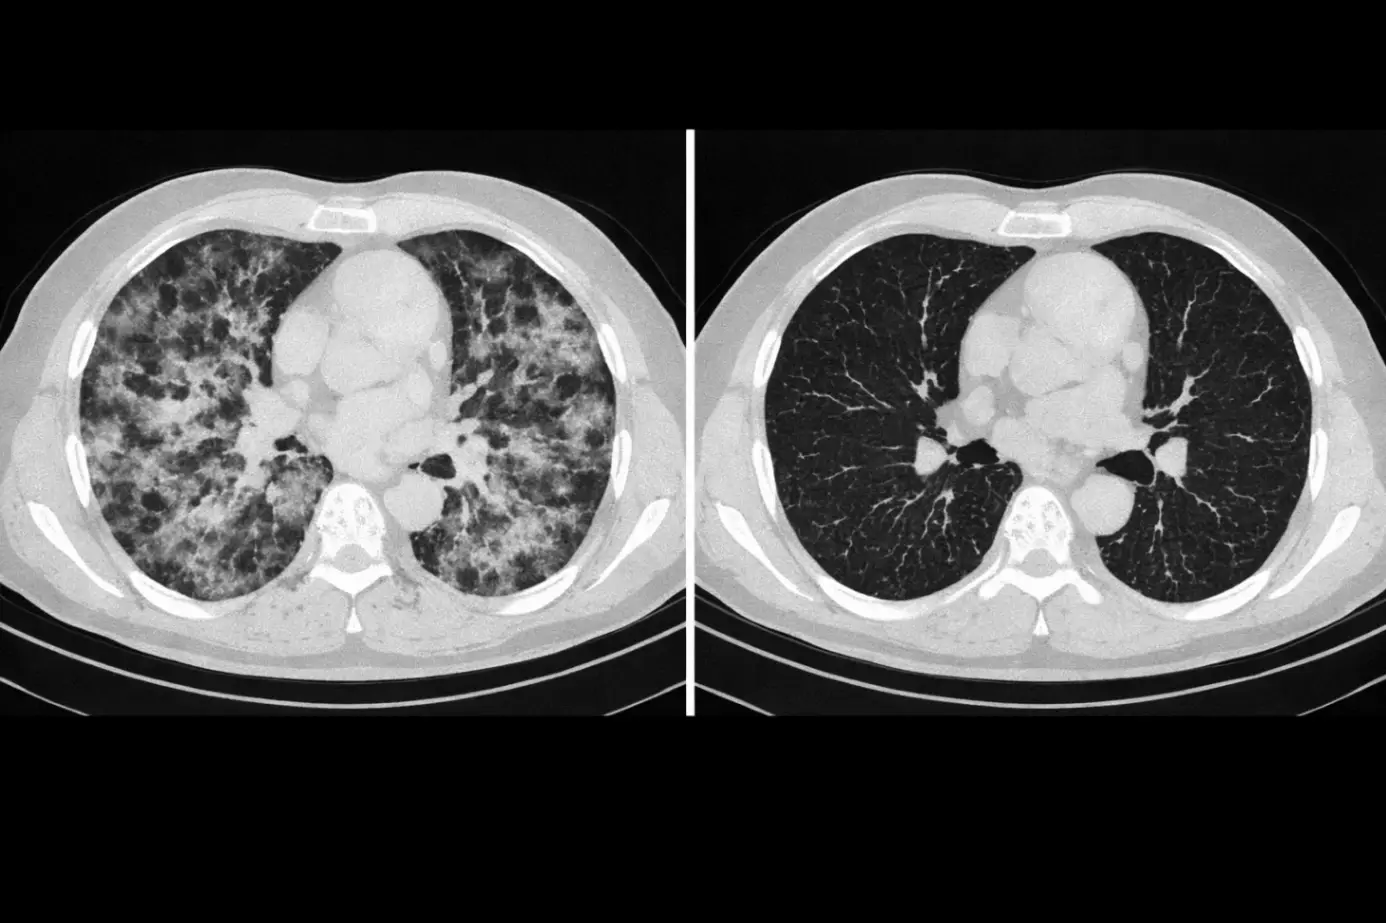

В пульмонологии динамика тоже играет огромную роль. Узлы в лёгких, поствоспалительные изменения, фиброз, осложнения после инфекций — всё это может развиваться незаметно. ИИ умеет сравнивать КТ лёгких по датам и выделять зоны, которые увеличились или изменили плотность. Это даёт врачу более уверенную основу для наблюдения и снижает риск «пропустить» проблему в самом начале.

Главная сила ИИ — количественная оценка. Там, где врач видит «чуть больше», алгоритм способен вычислить изменение объёма очага, площади поражения или плотности ткани. Это особенно важно при наблюдении опухолей, метастазов, узлов в лёгких, изменений в печени и других органах. Такой подход делает динамику более понятной, потому что она выражена цифрами и сравнением «до/после». А цифры легче контролировать, обсуждать и использовать в протоколах лечения.

Чтобы динамика была корректной, ИИ учитывает технические нюансы: различия в толщине среза, шум изображения, уровень контрастирования, артефакты. В современных системах применяются модели сегментации, которые «обводят» интересующую область, а затем сравнивают её между датами. Это позволяет не просто искать изменения в целом снимке, а анализировать конкретный очаг или орган. Врач при этом получает подсказку, где именно произошло изменение и насколько оно значимо.